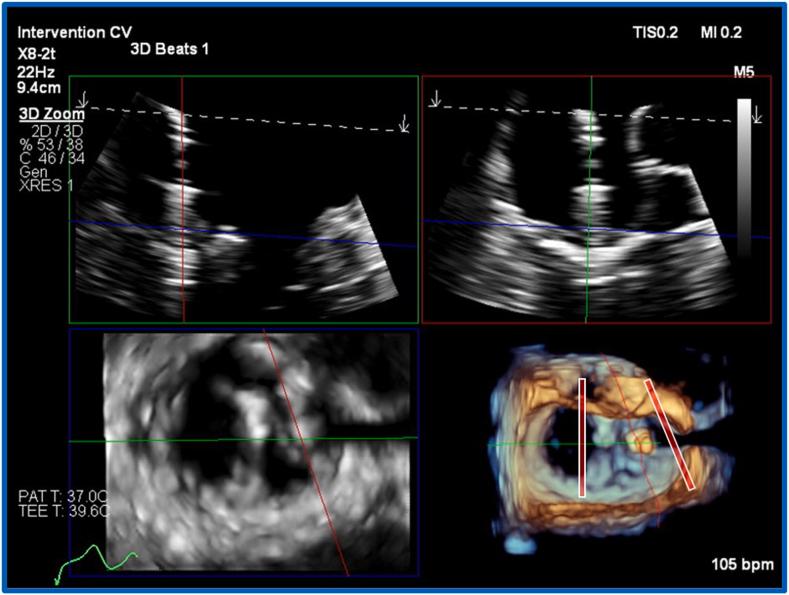

用于具有挑战性的二尖瓣经导管缘对缘修复术中引导的三维实时多平面重建

Three-Dimensional Real-Time Multiplanar Reconstruction for Intraprocedural Guidance of Challenging Mitral Transcatheter Edge-to-Edge Repair.

• 3D MPR allows simultaneous viewing and manipulation of intersecting 2D planes. • Mitral TEER demands intuitive anatomic displays and optimal imaging precision. • 3D RT-MPR simplifies complex multidevice and unfavorable anatomy cases. • Lower resolution in the 3D-derived 2D planar images is a current limitation.

摘要

• 三维多平面重组(3D MPR)允许同时查看和操作相交的二维平面。

• 二尖瓣经导管边缘对边缘修复术(Mitral TEER)需要直观的解剖显示和最佳的成像精度。

• 三维实时多平面重组(3D RT-MPR)简化了复杂的多装置和解剖结构不佳的病例。

• 三维衍生二维平面图像的分辨率较低是目前的一个限制。